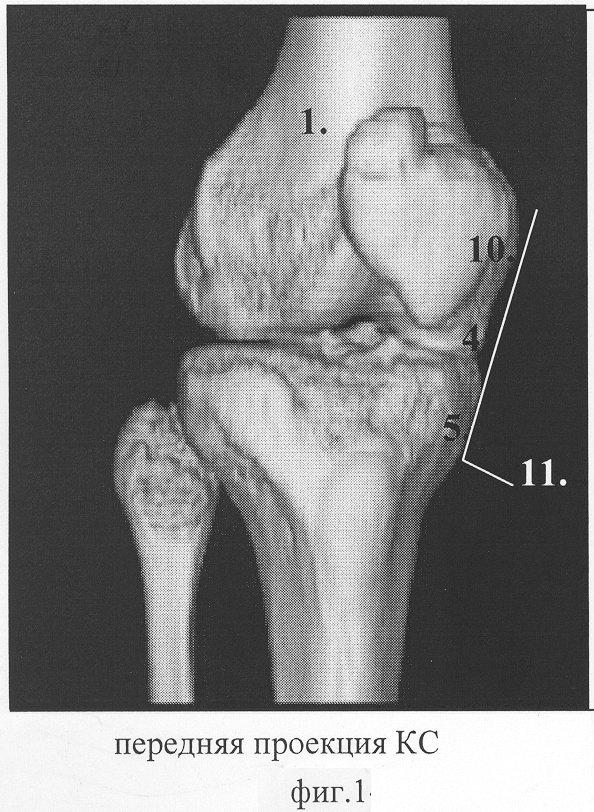

Способ пояснен на фиг.1 – передняя проекция коленного сустава; фиг.2 – боковая проекция коленного сустава; фиг.3 – позиция линейного датчика по линии пересечения медиального мыщелка бедренной кости и медиального мыщелка большеберцовой кости; фиг.4 – позиция указанного датчика, смещенного в область суставной щели в зоне расположения переднего рога внутреннего мениска; фиг.5 – позиция указанного датчика, под углом 30° в зоне расположения тела внутреннего мениска; фиг.6 – эхограмма неизмененного переднего рога и тела внутреннего мениска.

На фиг.1, 2, 3, 4, 5, 6 приняты следующие обозначения:

1 – коленный сустав;

2 – линейный датчик;

3 – внутренняя суставная щель;

4 – дистальный отдел медиального мыщелка бедренной кости коленного сустава;

5 – проксимальный отдел медиального мыщелка большеберцовой кости коленного сустава;

6 – первая позиция, датчик в положении переднего рога внутреннего мениска;

7 – передний рог внутреннего мениска;

8 – вторая позиция, датчик в положении тела внутреннего мениска;

9 – тело внутреннего мениска;

10 – нижний медиальный полюс надколенника;

11 – линия, проведенная между дистальным отделом медиального мыщелка бедренной кости 4 и проксимального отдела медиального мыщелка большеберцовой кости 5 коленного сустава 1.

На фиг.1, 2, 3, 4, 5, 6 на коленный сустав 1 устанавливают линейный датчик 2 в проекции внутренней суставной щели 3, расположенной между дистальным отделом медиального мыщелка бедренной кости 4 коленного сустава 1 и проксимального отдела медиального мыщелка бедренной кости 5 коленного сустава 1. Фиксируют датчик 2 в первой позиции 6 в положении переднего рога 7 внутреннего мениска. Во второй позиции 8 датчик 2 устанавливают в положении тела внутреннего мениска 9 коленного сустава 1 между дистальным отделом медиального мыщелка бедренной кости 4 коленного сустава 1 и нижним медиальным полюсом надколенника 10, соответствующая линии 11.

– линию 11, фиг.1, проведенную между медиальным мыщелком бедренной кости 4 и медиальным мыщелком большеберцовой кости 5.